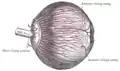

سلولهای استوانه و مخروط شبکیه از راه عصبهای دوقطبی به سلولهای گانگلیونی رسیده و پس از آن عصب بینایی شکل گرفته، وارد فضای کرانیکال شده و در تماس با سلا تورسیکا به طرف نواحی فوقانی مغز یا قسمتهای پایین تر مغز است. یک عصب بینایی حاوی حدود یک میلیون آکسون است. فیبرهای نیمه بینی از هر دو شبکیه، در ناحیه کیاسمای بینایی(Optic chiasma) تقاطع میکنند و به طرف مقابل میروند و به فیبرهای نیمه گیجگاهی(تمپورال) همان طرف میپیوندند و بدین ترتیب، راه بینایی(Optic tract) را در هر طرف ایجاد میکنند. نسبت رشتههای متقاطع به غیرمتقاطع، ۵۳ به ۴۷ بوده و تعداد سلولهای گانگلیونی نیمه بینی(نازال) شبکیه بیشتر است[4].

اکثر فیبرهای راه بینایی(حدود ۹۰%) جهت انتقال پیامها به قشر بینایی، ابتدا وارد هسته زانویی خارجی[5] تالاموس میگردند. بقیه فیبرها به بخشهای پایین تر مغز وارد میشوند.